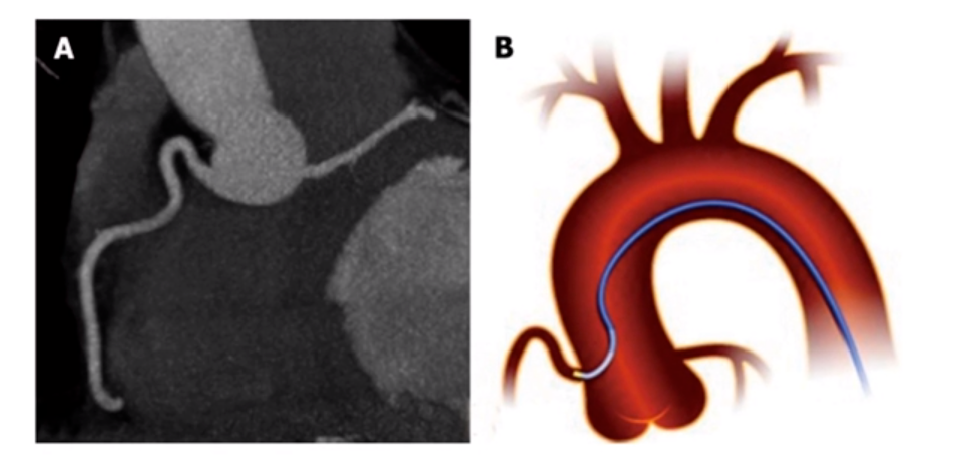

桥血管示意图:

图6